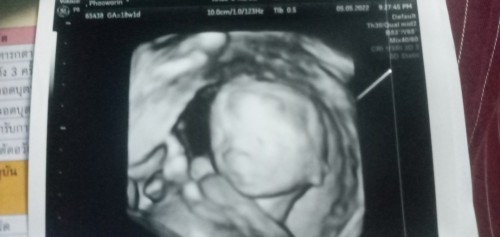

ภาพ ซาวตอน5เดือน มีใครเหมือนบ้านนี้มั้ยคะ ในถาพน้องจะท้องใหญ่ แต่คุณหมอไม่ได้แต้งอะไรค่ะ เป็นปกติมั้ยคะ มีอม่ๆคนไหนเป็นเหมือนกันบ้างคะ

18วีคค่าา ท่าฮิตเลยค่ะแม่

13วีคค่ะน้องตัวใหญ่ปกติดีค่ะแม่